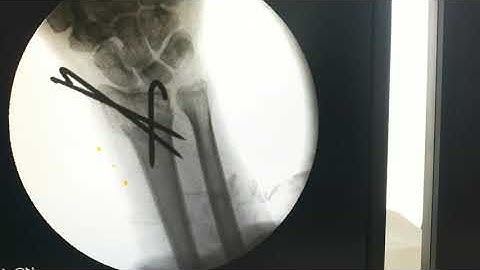

Distal Radius Fracture K wiring and External Fixator | Dr. Prateek Joshi